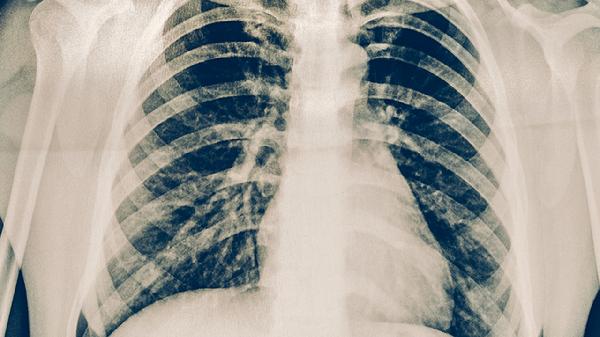

支气管肺炎的典型表现包括发烧、咳嗽、咳痰、呼吸加快和胸部不适。这些症状大多由病原体感染引发,需要通过临床检查来确认诊断。...

支气管肺炎在临床上常表现出一系列典型症状,包括咳嗽、发热、呼吸急促、胸痛以及肺部的异常声音。这些表现会随着病情的发展分为...